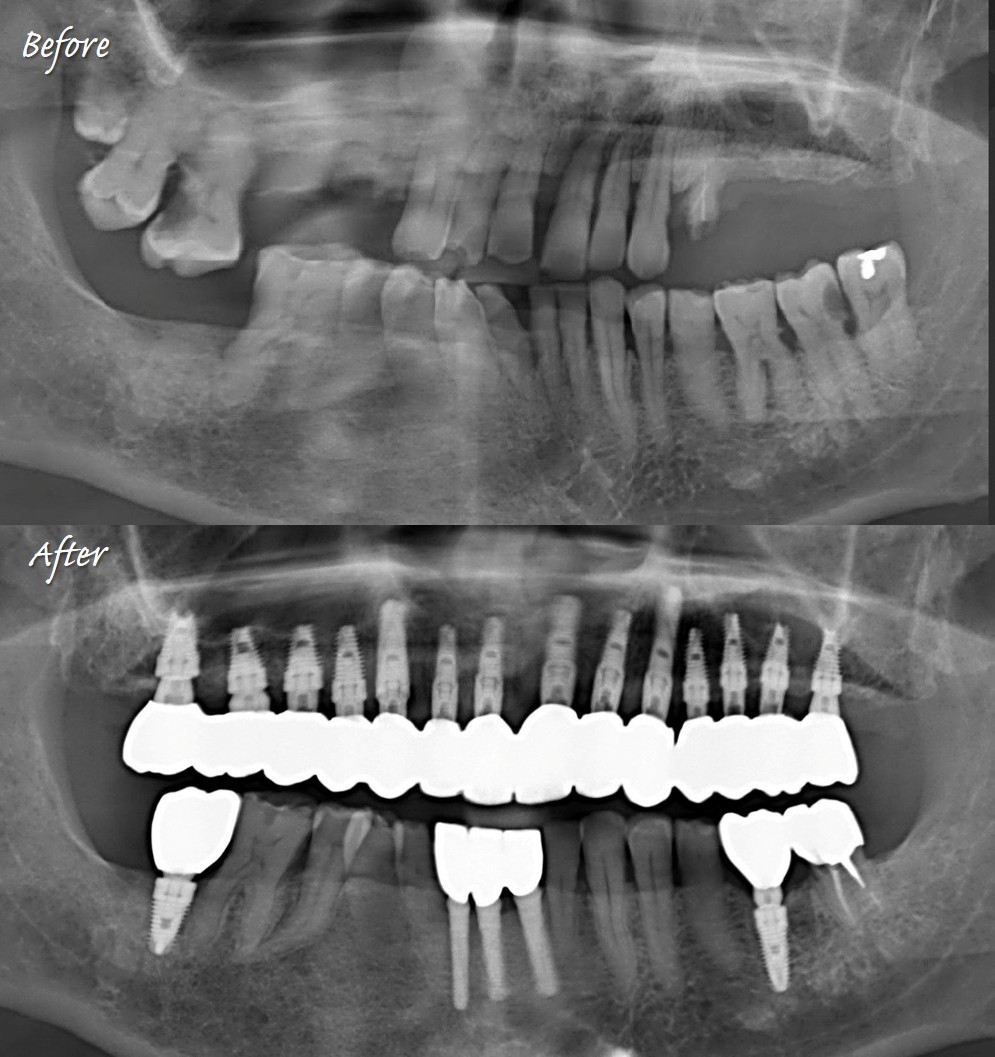

這樣的植牙方式,5 in 1:即拔即植加上同時補骨、推鼻竇與接臨時假牙出來。除了陳博士以外,也慢慢有優秀的學生做得到了。

與坊間全口重建常見到的all on X最不同的是,這才是最禁得起時間考驗的「一冠一釘」。紮紮實實又直挺挺的植體,而不是歪歪斜斜的植牙受力,真正的令人放心。